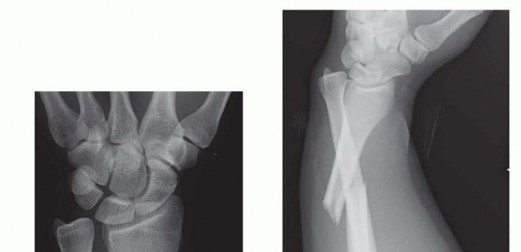

Reduction and Stabilization of the Distal Radioulnar Joint following Galeazzi Fractures